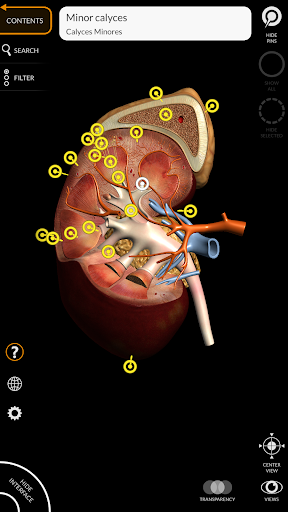

"Anatomy 3D Atlas" vous permet d'étudier l'anatomie humaine de manière simple et interactive.

Grâce à une interface simple et intuitive, il est possible d'observer chaque structure anatomique sous n'importe quel angle.

Les modèles anatomiques 3D sont particulièrement détaillés et avec des textures jusqu'à une résolution de 4k.

La subdivision par régions et les vues prédéfinies facilitent l'observation et l'étude de parties individuelles ou de groupes de systèmes et les relations entre différents organes.

• Système urogénital (homme et femme)

• Faites pivoter et zoomez chaque modèle dans l'espace 3D

• Option pour masquer ou isoler un ou plusieurs modèles sélectionnés

• Filtrez pour masquer ou afficher chaque système

• Fonction de recherche pour trouver facilement chaque partie anatomique

• Fonction de transparence